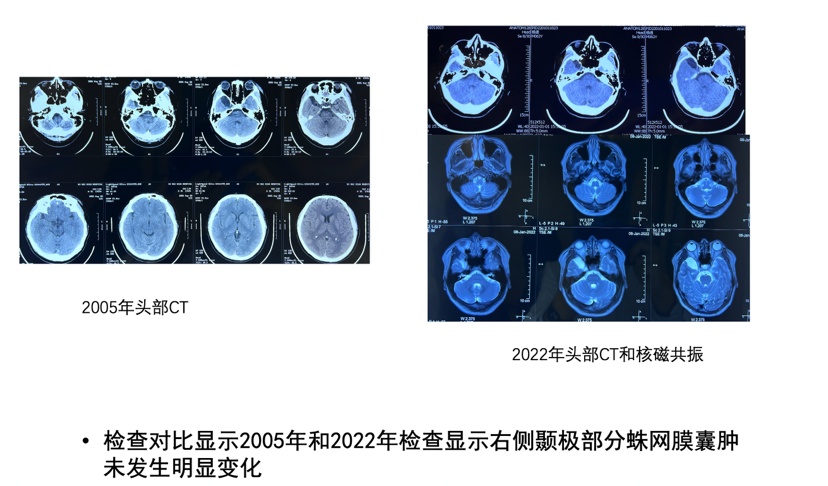

病例三 患者男性,右侧侧裂蛛网膜囊肿,35岁发现蛛网膜囊肿,没有症状一直观察,每3-5年复查,最近一次复查后影像学没有任何变化,症状没变化(发现病灶跨度17年)